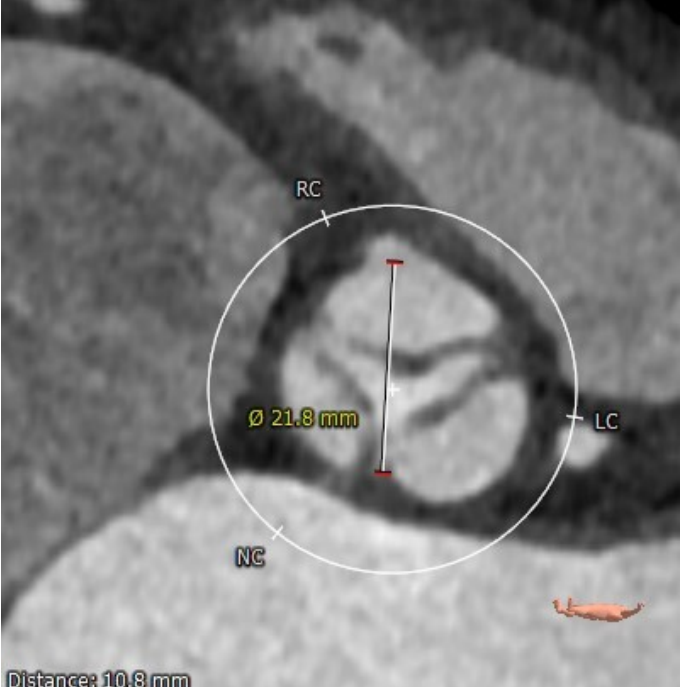

瓣环

周长:68.1mm 平均直径:21.7mm

法氏窦

直径:25.3*24.2*25.1mm

窦管结合部

平均直径:25.8mm

升主动脉

平均直径:31.9mm

左冠高度高度:14.6mm

右冠高度高度:9.8mm

主动脉瓣角度 44°

钙化积分68mm³